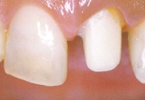

■CASE-2.(インプラント上部構造)

症例のような顕著な着色歯の場合も、Sinfonyは色を混和することで患者固有の色調を

忠実に再現することができます。

[術前] [アパッチメント装着] [術後]